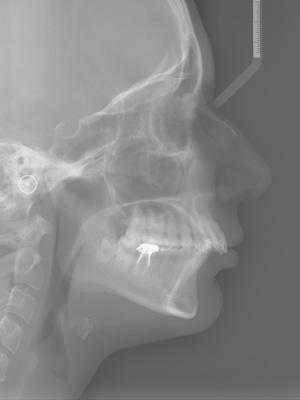

Для дифференциальной диагностики разновидности дистального прикуса проводится телерентгенография с последующим анализом и расчетом рентгенцефалометрических показателей; определение конструктивного прикуса; изготовление и исследование диагностических моделей челюстей. С целью оценки состояния элементов височно-нижнечелюстного сустава и жевательных мышц используется рентгенография или томография ВНЧС, электромиография, реография.

Для оценки состояния прикуса и определения его вида в первую очередь проводится визуальный осмотр зубов и полости рта стоматологом-ортодонтом и сбор информации от пациента. При первичном осмотре врач также обращает внимание на состояние сустава, осанку, признаку нарушения носового дыхания. Для дальнейших расчётов и составления плана лечения нужны более точные данные, которые можно поучить с помощью современных диагностических методов.

Дистальное положение челюстей на телерентгенограмме

- Компьютерная томография или 3D-проекция черепа. По ней можно оценить важные показатели для ортодонтического лечения: клиническую форму прикуса, размер и положение челюстей. Положение и соотношение зубов в костной ткани и ее объемы. Состояние и положение головки височно-нижнечелюстного сустава. Трехмерная модель черепа дает более точное представление о положении зубов и челюстей, чем классических 2D-снимок черепа в боковой проекции.